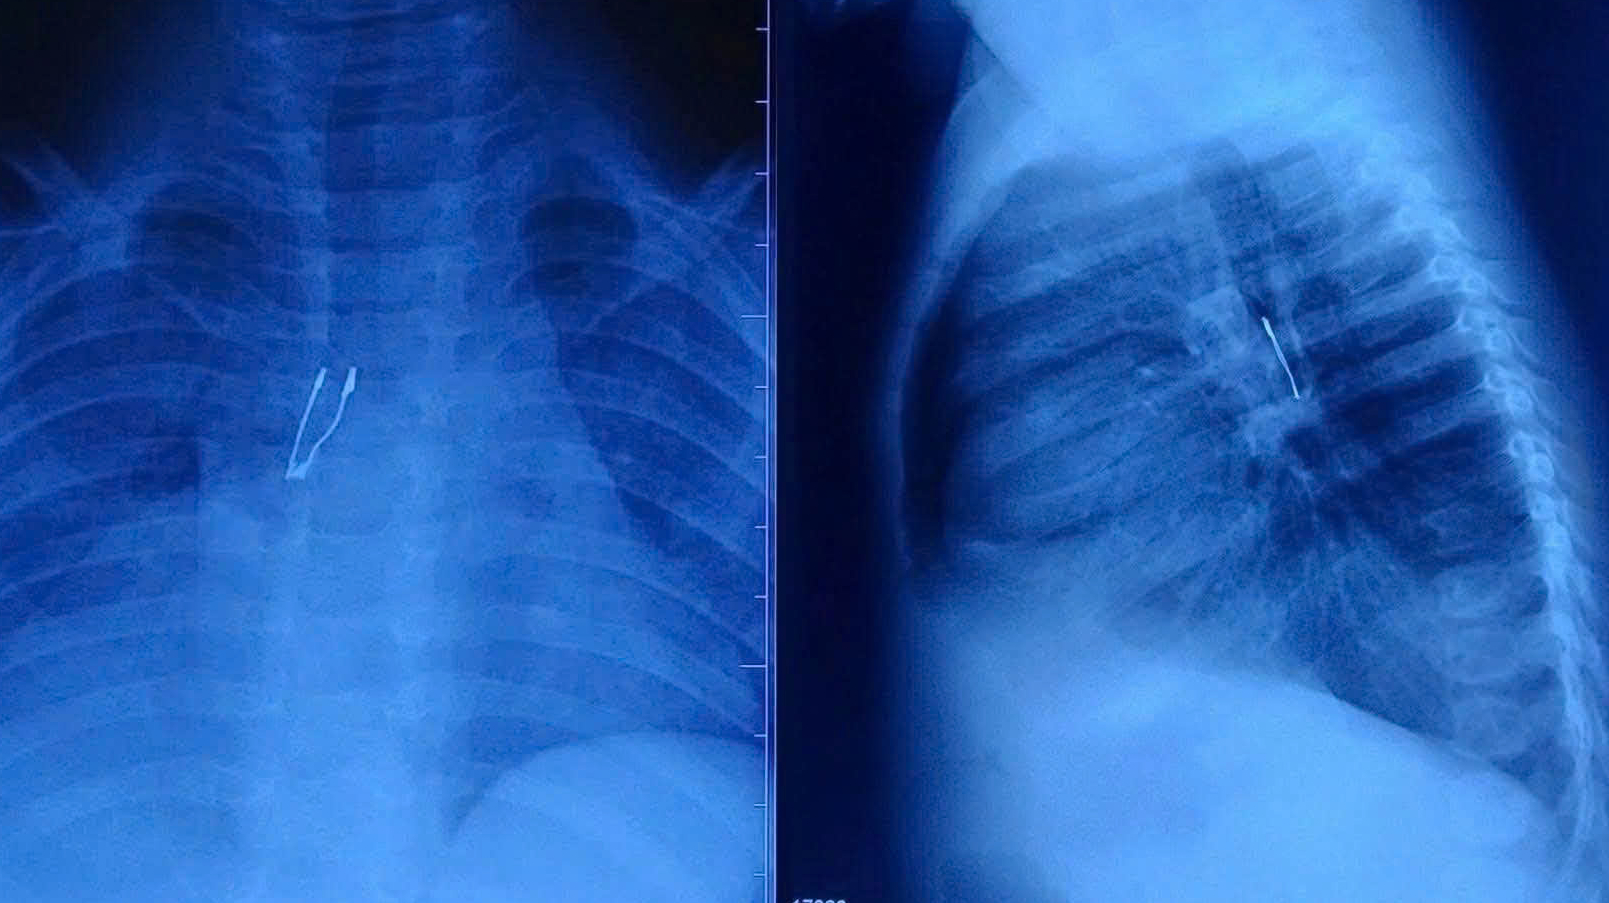

Theo BS.CKI Lý Phạm Hoàng Vinh – khoa Tai Mũi Họng, bệnh nhi N.K.N. (9 tháng tuổi, Đồng Tháp) nhập viện sau 2 ngày ho nhiều. Trước đó, tại tuyến dưới, bệnh nhi được chụp phim X-quang phát hiện bất thường nghi dị vật đường thở nên được chuyển lên tuyến trên. Gia đình không ghi nhận rõ thời điểm trẻ sặc cũng như loại dị vật.

Tại Bệnh viện Nhi đồng 1, kết quả chẩn đoán cho thấy dị vật cản quang nằm ở phế quản gốc phải, kèm dấu hiệu xẹp phổi phải chưa hoàn toàn và tràn khí trung thất – những biến chứng tiềm ẩn nguy cơ nặng. Ngay lập tức, ê-kíp Khoa Tai Mũi Họng đã hội chẩn liên chuyên khoa, phối hợp gây mê tiến hành nội soi phế quản cấp cứu.

Hình ảnh dị vật nằm sâu trong phế quản. Ảnh: BVCC.

Dị vật được xác định là một bóng đèn LED mắc kẹt sâu trong phế quản gốc phải. Quá trình gắp gặp nhiều khó khăn do cấu trúc đuôi đèn bè, sắc nhọn, dễ gây tổn thương khi kéo qua thanh quản. Với đường thở của trẻ còn rất nhỏ, bác sĩ phải xoay chỉnh dị vật từng chút một để đưa phần đầu ra trước, hạn chế tối đa nguy cơ trầy xước hoặc rách niêm mạc.